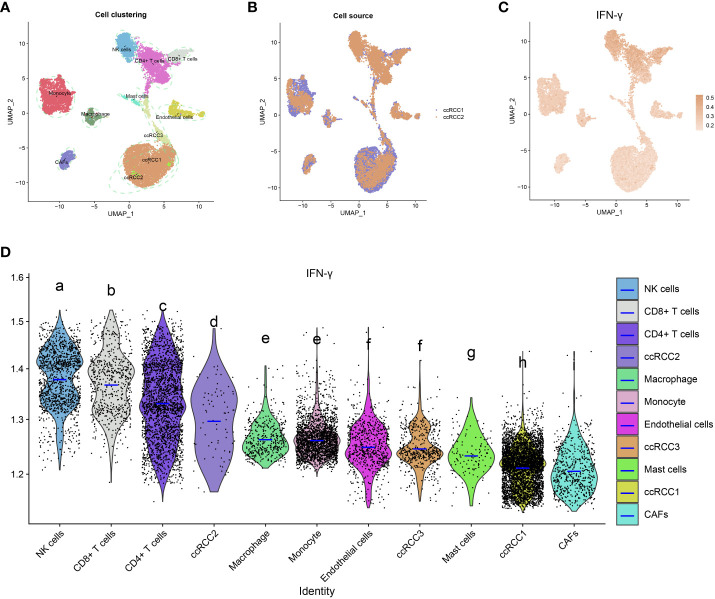

Single-cell transcriptome analysis of IFN-γ in KIRC tumor microenvironment

Quality control was performed by Seurat, and then 13124 high-quality single-cell transcriptomic data were selected for further analyses. The aforementioned cells may be classified into 11 groups, as determined by a tSNE-based cell clustering analyses: monocyte1, monocyte2, KIRC1, KIRC2, KIRC3, macrophages, mast cells, endothelial cells, NK cells, CD4+T cells, and CD8+T cells (f13). Variations in marker gene expression were highly significant across cell types (Supplementary Figure 9). We also discovered that cancerous cells from two independent KIRC samples cluster together into the same cluster (KIRC3) as well as many other distinct clusters (KIRC1 and KIRC2). The above findings demonstrate the heterogeneity within the KIRC cell type (f13). To assess the variations in IFN-γ scores across cell types, we conducted ssGSEA to summarize the IFN- scores of cells in the KIRC TME. Notably, we found significant differences in IFN-γ scores among different cells (f13). KIRC cells had the least IFN-γ score, suggesting that this marker more accurately represented the TME than the tumor itself. IFN-γ scores varied significantly across KIRC cell subsets, suggesting that IFN-γ expression is a potential KIRC cell characteristic (f13). Based on this analysis, it appears that IFN-γ is significantly different among different cells of KIRC TME. As a consequence, targeting IFN-γ could represent a substantial step forward in TME regulation.